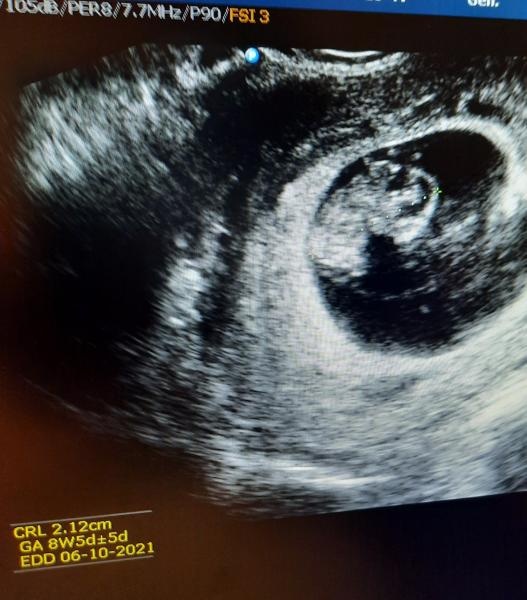

Så härligt att några har varit och fått se era små på ul! :)

Jag var oxå i måndags,allt såg bra ut då <3 Gick in i vecka 10 idag!